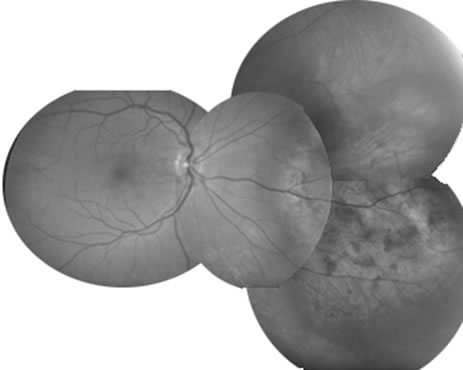

1. The intraocular findings in primary intraocular–CNS lymphoma may simulate a diffuse uveitis, usually with a plethora of vitreous cells and often with virtually pathognomonic yellowish white chorioretinal infiltrates (Fig. 20). Less common clinical presentations can mimic toxoplasmosis, acute retinal necrosis, a branch vein occlusion, or various forms of retinal vasculitis.

Fig. 20. Yellowish white chorioretinal infiltrate typical of primary intraocular lymphoma (erroneously termed ocular reticulum cell sarcoma). (Char DH: Clinical Ocular Oncology. 2nd ed. Philadelphia, Lippincott-Raven, 1996.)